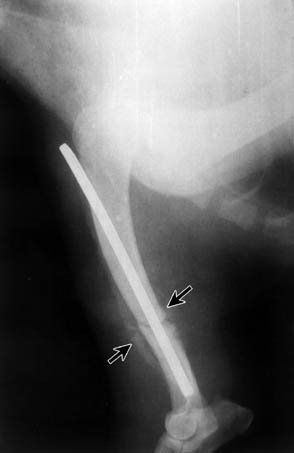

Between weeks 2 and 4, twenty dogs (90%) radiologically presented an irregular-shaped periosteal reaction with new bone formation (Fig. 1). A characteristic feature was that this occurred far from the fracture site, along the bone. In some cases, there were spicule-like formations with denser shadows (Figs. 2 and 5). In the event that a fragment of a comminuted fracture became necrotic, that is, that it turned into a primary sequestrum, it was surrounded by a dense shadow - a product of the periosteum (Fig. 3). During the development of osteomyelitis we observed a loosening of fixation implants in 15 dogs (68%). On radiographs, the condition was seen as zones of radiolucency around the implants, and after destabilisation of fractures - there was a formation of a callus in the place of mobility without healing (Fig. 4).

Fig. 1. Lateral radiograph of the humerus in patient 33/02.11.93, two weeks after osteosynthesis. The arrows show an irregular-shaped periosteal reaction.

Fig. 2. Lateral radiograph of the humerus in patient 33/02.11.93, three weeks after osteosynthesis. The arrows show spicule-like formations - a product of the periosteum.

The radiological studies were performed over a long period of time (up to 4 months). The characteristic features in almost every sick animal were that, together with osteolysis, a periosteal reaction developed. In the beginning, the periosteum became elevated due to the exudate (Figs. 1 and 2) which exited through the Haversian and Folkmann channels.